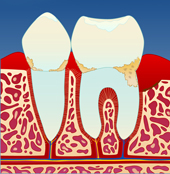

Utviklingen av periodontitt Mangelfullt renhold kan gi en overfladisk betennelse i tannkjøttet ( gingivitt ). Tannkjøttet blir da hovent og får en mørkere rødfarge. Det vil også blø ved berøring og føles ømt. Dette skyldes bakterier og mykt belegg som blir liggende langs tannkronen (I).

| |  | |  | |  |

| figur I | | figur II | | figur III | | figur IV |

Dersom belegget ikke fjernes, vil det over tid forkalkes og bli hardt. Det er dette vi kaller tannstein. Tannstein forsterker betennelsen som fører til at benet rundt tennene brytes ned (II). På denne måten vil tannstein og bakteriebelegg kunne strekke seg stadig lenger ned langs rotoverflaten (III). Bentapet kan over tid bli så omfattende at tenner løsner og eventuelt må fjernes (IV).